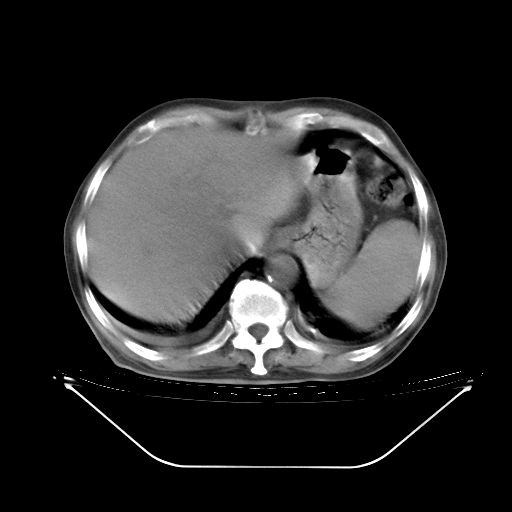

今天复查肺部CT,发现双肺广泛磨玻璃样改变。所以我把3月19日和5月9日相隔50天的肺部CT上传。请大家会诊。

5月9日肺部CT(在4月27日齐鲁医院肺部CT描述部分肺组织磨玻璃样改变,12天后肺组织广泛磨玻璃样改变)

大致读了系列胸部CT:纵隔窗无明显异常,肺窗:从4、27至今:主要是双肺中下野外带可见毛玻璃样改变,目前处于急性肺泡炎阶段,至于原因考虑1、结替组织或胶原血管性疾病所致?2、恶性疾病如恶组在肺部所致的表现或细支气管肺泡癌?3、药物或其它原因如肺蛋白沉着症所致肺泡炎目前不太可能?总之,明天就去请我院的呼吸科、感染科、血液科和临免专家会诊哈。